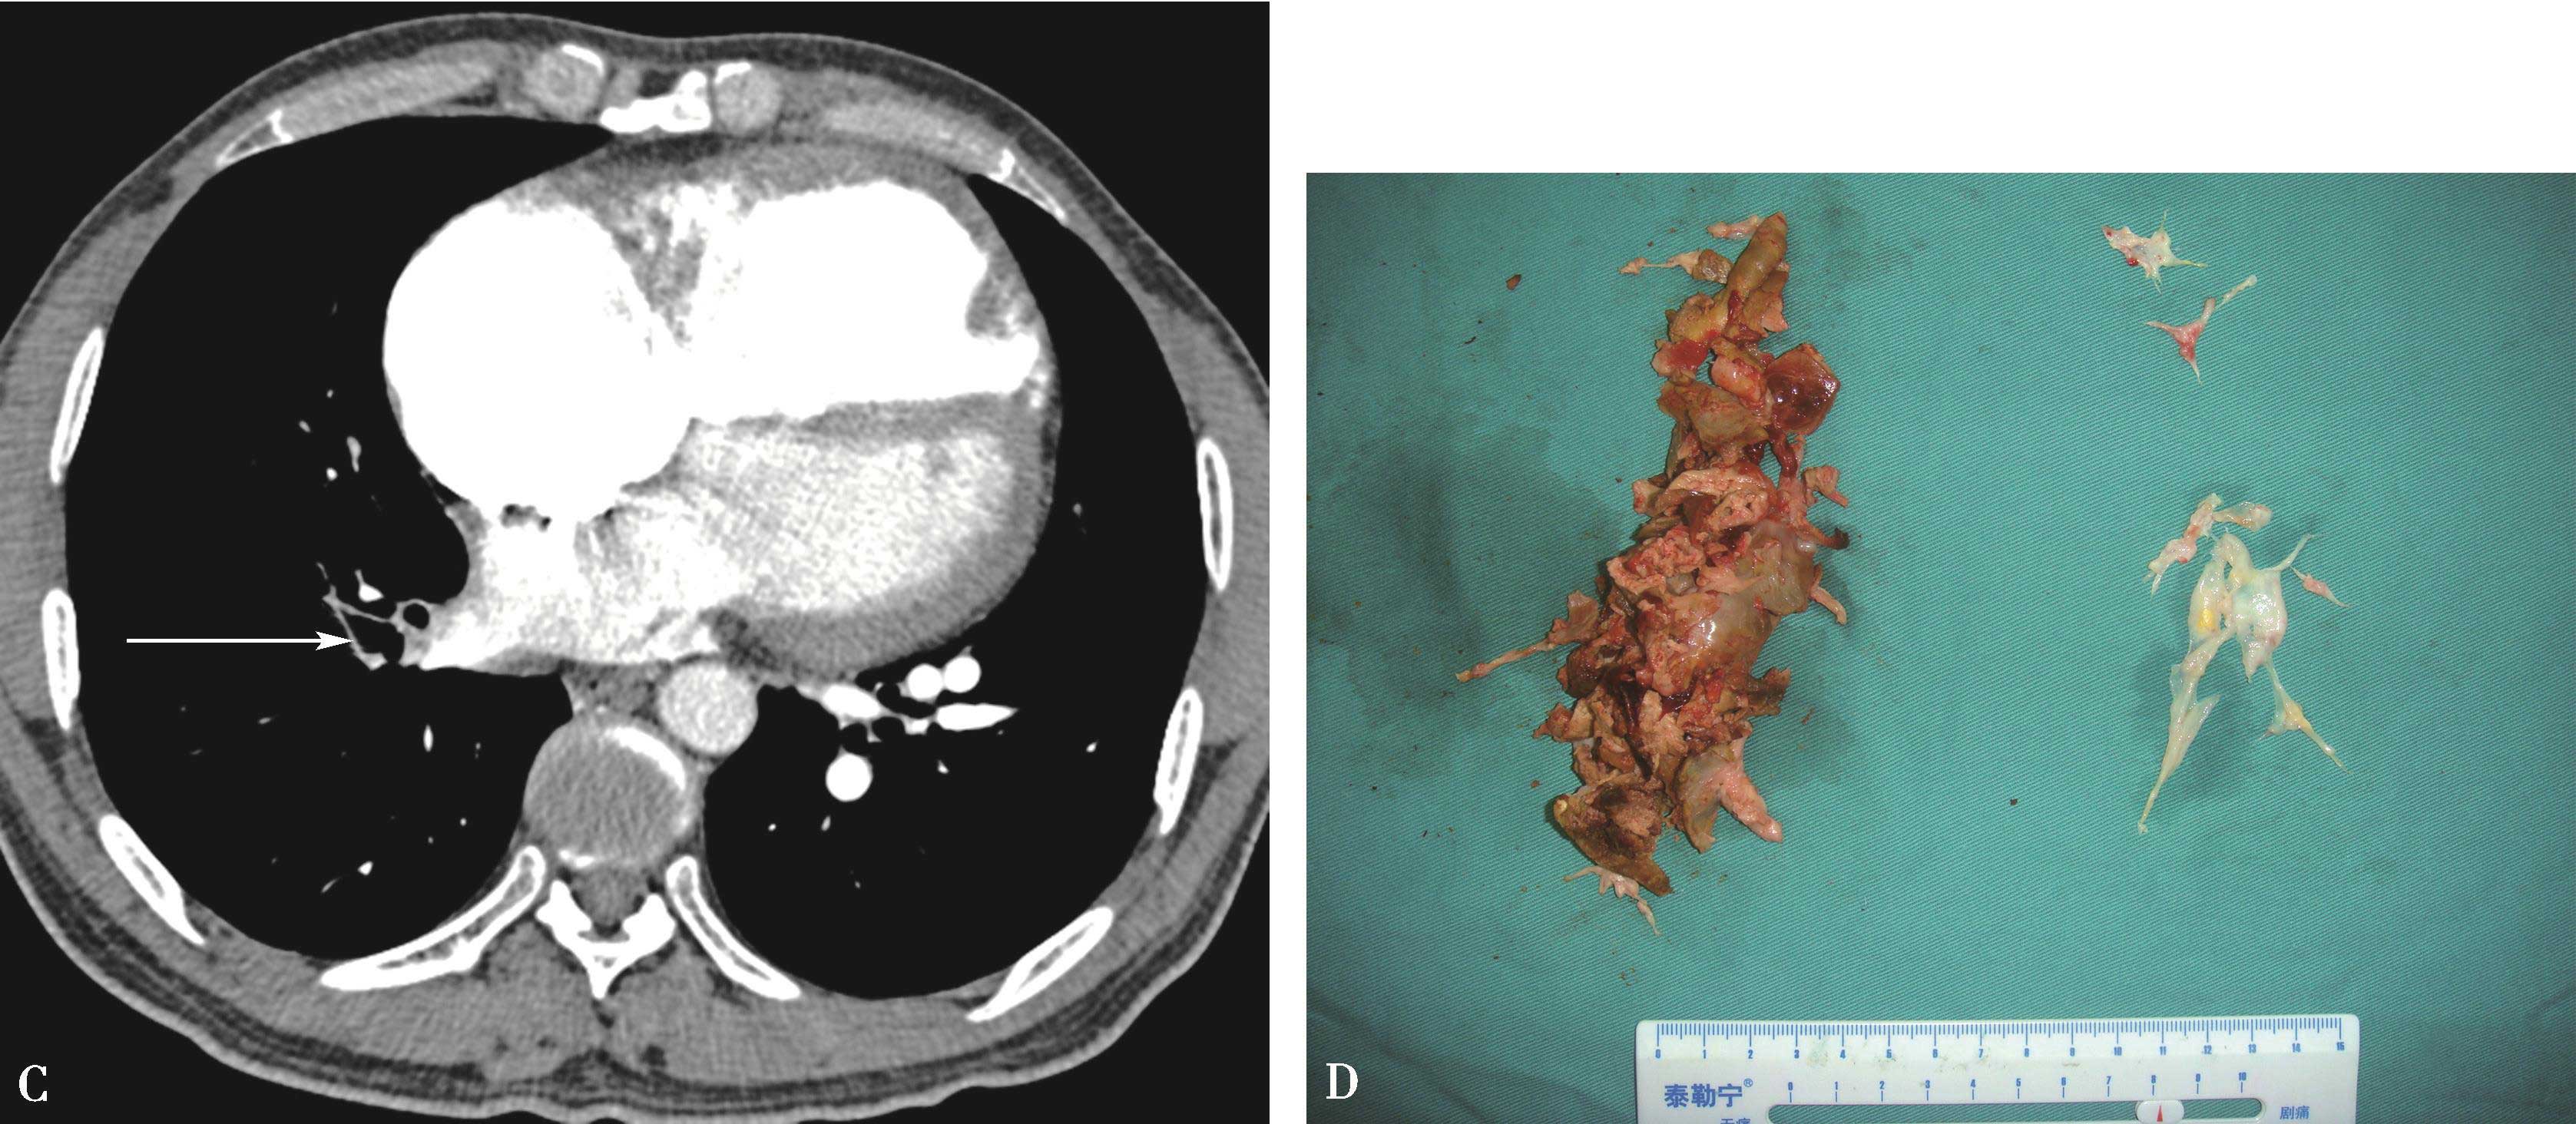

图8-7-1 女,21岁,反复咯血2年,胸闷气短1年半

CT横断扫描。A、B.多层重组;C、D.示主肺动脉及左右肺动脉内结节状充盈缺损,可见 “指压征”(↑),右肺动脉及左下肺动脉闭塞;前上纵隔中等密度影,考虑为纵隔转移(A▲)。肺动脉造影(E)示主肺动脉不规则充盈缺损,右肺动脉及左下肺动脉闭塞,术后病理诊断:低分化平滑肌肉瘤(F)

图8-7-2 男,44岁,因劳力性胸闷、气短2年余,加重1个月并出现双下肢水肿急诊入院

CT横断扫描ABCD示主肺动脉、右肺动脉干内巨大充盈缺损,膨胀性生长,累及右心室流出道(↑),主肺动脉明显扩张。肺动脉造影E,示主肺、左右肺动脉干及右下肺动脉管腔内充盈缺损(↑),两肺、左肺舌叶及下叶各基底支仅见稀疏肺动脉分支显影。病理诊断为恶性间叶细胞瘤。

图8-7-3 女,53岁,劳力性呼吸困难2个月余,偶尔咯血

A.CT横断图像,示主肺动脉及右肺动脉内充盈缺损-闭塞(↑);B.磁共振TIWI显示主肺动脉及右肺动脉中等信号(↑);C.磁共振增强扫描。管腔内充盈缺损,充盈缺损信号不均匀增强(↑);D. 18 F-FDG PET检查示该病灶呈放射性浓集(↑);E.手术切除大体标本,白色为瘤体;F.病理证实为原发肺动脉肉瘤。PA:主肺动脉;LPA:左肺动脉;RPA:右肺动脉